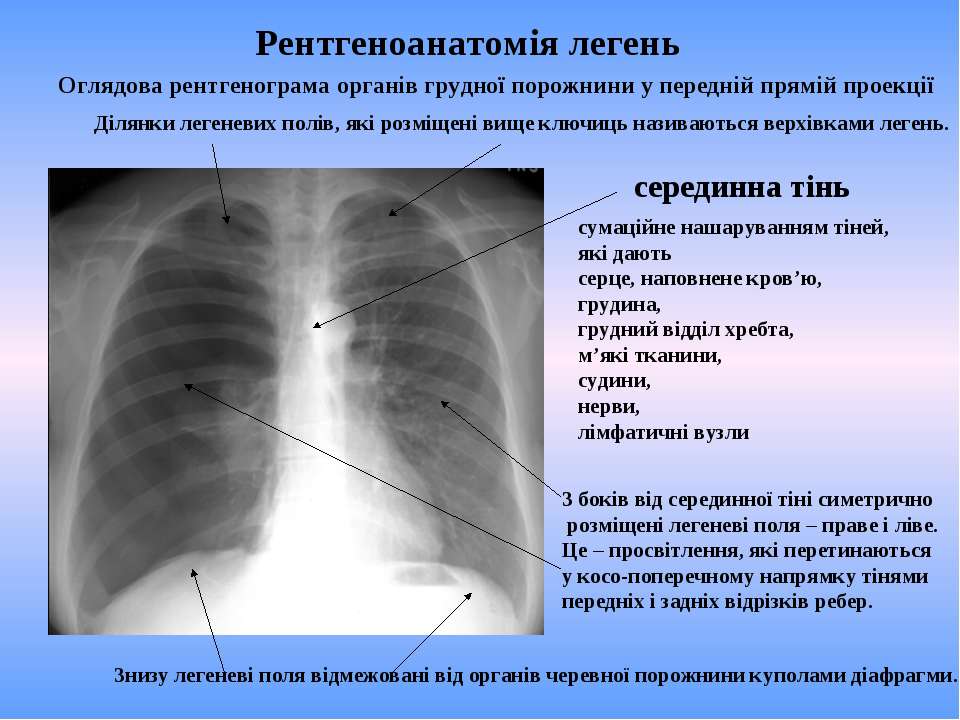

Диагностика плеврального выпота: что нужно знать